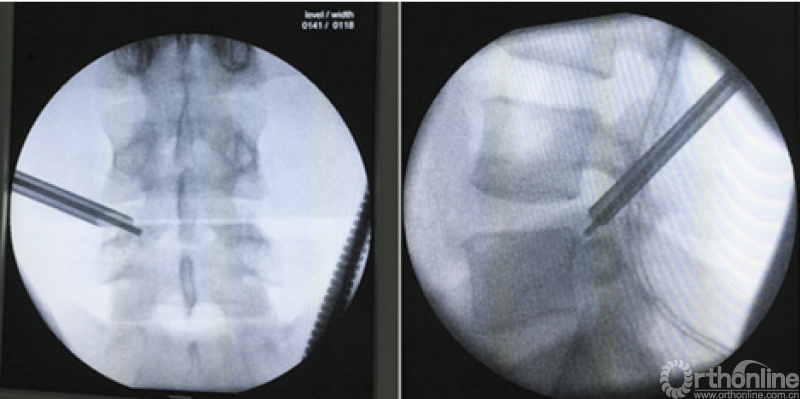

北京海淀医院微创脊柱外科,共纳入65例应用全内窥镜治疗的伴有坐骨神经痛的腰椎间盘突出症患者,随机分成行内镜手术并在神经根局部应用类固醇激素的实验组和只进行内镜手术的对照组,试验组全部采用经椎间孔入路内镜手术,在摘除突出髓核,处理纤维环并探查松解受累神经根见周围松弛无卡压后在术区局部神经根周围注入曲安奈德20mg。